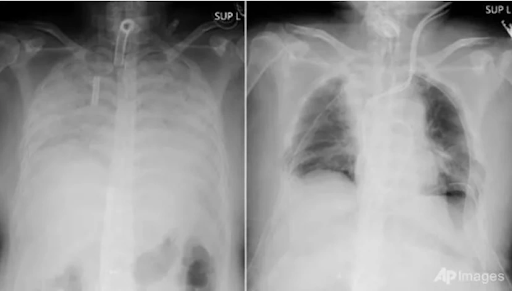

Hội chứng phổi trắng (thường được mọi người gọi là bệnh phổi trắng hay phổi khô) là chỉ tình trạng phổi có màu trắng xoá trên phim chụp X quang.

Chụp X quang phổi là một kỹ thuật quen thuộc trong y khoa. Máy chụp X quang sẽ phát ra những chùm tia X bức xạ cao xuyên qua các cơ quan, dựa trên mức độ hấp thụ và phản hồi của tia X mà cho ra hình ảnh các cơ quan như: phổi, tim, mạch máu,.. trên phim X quang. Các cơ quan, tổ chức bên trong lồng ngực sẽ hiển thị trên phim X quang với các màu sắc trắng, xám, đen với mức độ đậm nhạt khác nhau.

Bình thường, một lá phổi khỏe mạnh khi chụp phim X-quang, thì sẽ thấy phổi trong (hình ảnh hiển thị máu đen). Tuy nhiên, do viêm phổi hoặc bệnh lý khác dẫn đến phim phổi có hình ảnh trắng bất thường.

| Hình ảnh X-quang phổi trắng (Ảnh minh họa) |